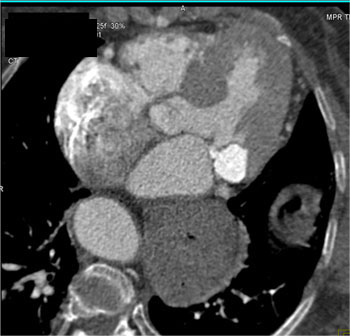

|  | Question 3: 87 yr old female with history of hypertension had negative stress echo, presents with acute chest pain. What’s the diagnosis? |